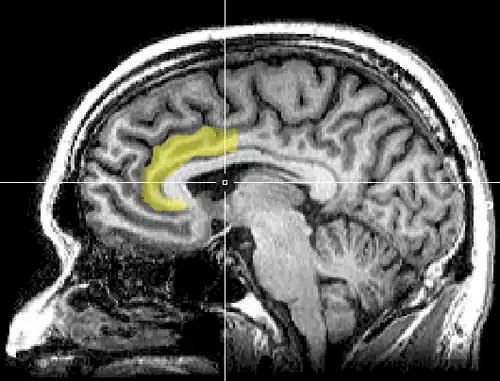

Cognitive dissonance produces a state of negative affect, which motivates the person to reconsider the causative behavior in order to resolve the psychological inconsistency that caused the mental stress.[125][126][127][128][129][130] As the affected person works towards a behavioral commitment, the motivational process then is activated in the left frontal cortex of the brain.[125][126][127][131][129]

The study Neural Activity Predicts Attitude Change in Cognitive Dissonance[133] (Van Veen, Krug, etc., 2009) identified the neural bases of cognitive dissonance with functional magnetic resonance imaging (fMRI); the neural scans of the participants replicated the basic findings of the induced-compliance paradigm. When in the fMRI scanner, some of the study participants argued that the uncomfortable, mechanical environment of the MRI machine nevertheless was a pleasant experience for them; some participants, from an experimental group, said they enjoyed the mechanical environment of the fMRI scanner more than did the control-group participants (paid actors) who argued about the uncomfortable experimental environment.[133]

The results of the neural scan experiment support the original theory of Cognitive Dissonance proposed by Festinger in 1957; and also support the psychological conflict theory, whereby the anterior cingulate functions, in counter-attitudinal response, to activate the dorsal anterior cingulate cortex and the anterior insular cortex; the degree of activation of said regions of the brain is predicted by the degree of change in the psychological attitude of the person.[133]

As an application of the free-choice paradigm, the study How Choice Reveals and Shapes Expected Hedonic Outcome (2009) indicates that after making a choice, neural activity in the striatum changes to reflect the person's new evaluation of the choice-object; neural activity increased if the object was chosen, neural activity decreased if the object was rejected.[134] Moreover, studies such as The Neural Basis of Rationalization: Cognitive Dissonance Reduction During Decision-making (2010)[48] and How Choice Modifies Preference: Neural Correlates of Choice Justification (2011) confirm the neural bases of the psychology of cognitive dissonance.[121][135]

The Neural Basis of Rationalization: Cognitive Dissonance Reduction During Decision-making[48] (Jarcho, Berkman, Lieberman, 2010) applied the free-choice paradigm to fMRI examination of the brain's decision-making process whilst the study participant actively tried to reduce cognitive dissonance. The results indicated that the active reduction of psychological dissonance increased neural activity in the right-inferior frontal gyrus, in the medial fronto-parietal region, and in the ventral striatum, and that neural activity decreased in the anterior insula.[48] That the neural activities of rationalization occur in seconds, without conscious deliberation on the part of the person; and that the brain engages in emotional responses whilst effecting decisions.[48]

Emotional correlations

The results reported in Contributions from Research on Anger and Cognitive Dissonance to Understanding the Motivational Functions of Asymmetrical Frontal Brain Activity[136] (Harmon-Jones, 2004) indicate that the occurrence of cognitive dissonance is associated with neural activity in the left frontal cortex, a brain structure also associated with the emotion of anger; moreover, functionally, anger motivates neural activity in the left frontal cortex.[126][34] Applying a directional model of Approach motivation, the study Anger and the Behavioural Approach System (2003) indicated that the relationship between cognitive dissonance and anger is supported by neural activity in the left frontal cortex that occurs when a person takes control of the social situation causing the cognitive dissonance. Conversely, if the person cannot control or cannot change the psychologically stressful stimulation, they are without a motivation to change the circumstance, then there arise other, negative emotions to manage the cognitive dissonance, such as socially inappropriate behavior.[126][137][136]

The anterior cingulate cortex activity increases when errors occur and are being monitored as well as having behavioral conflicts with the self-concept as a form of higher-level thinking.[138] A study was done to test the prediction that the left frontal cortex would have increased activity. University students had to write a paper depending on if they were assigned to a high-choice or low-choice condition. The low-choice condition required students to write about supporting a 10% increase in tuition at their university. The point of this condition was to see how significant the counter-choice may affect a person's ability to cope. The high-choice condition asked students to write in favor of tuition increase as if it were their completely voluntary choice. The researchers use EEG to analyze students before they wrote the essay, as dissonance is at its highest during this time (Beauvois and Joule, 1996). High-choice condition participants showed a higher level of the left frontal cortex than the low-choice participants. Results show that the initial experience of dissonance can be apparent in the anterior cingulate cortex, then the left frontal cortex is activated, which also activates the approach motivational system to reduce anger.[138][139]